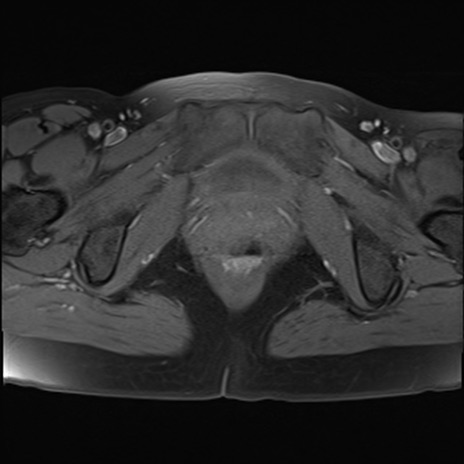

MRI(4日後)

T1WI(横断像)